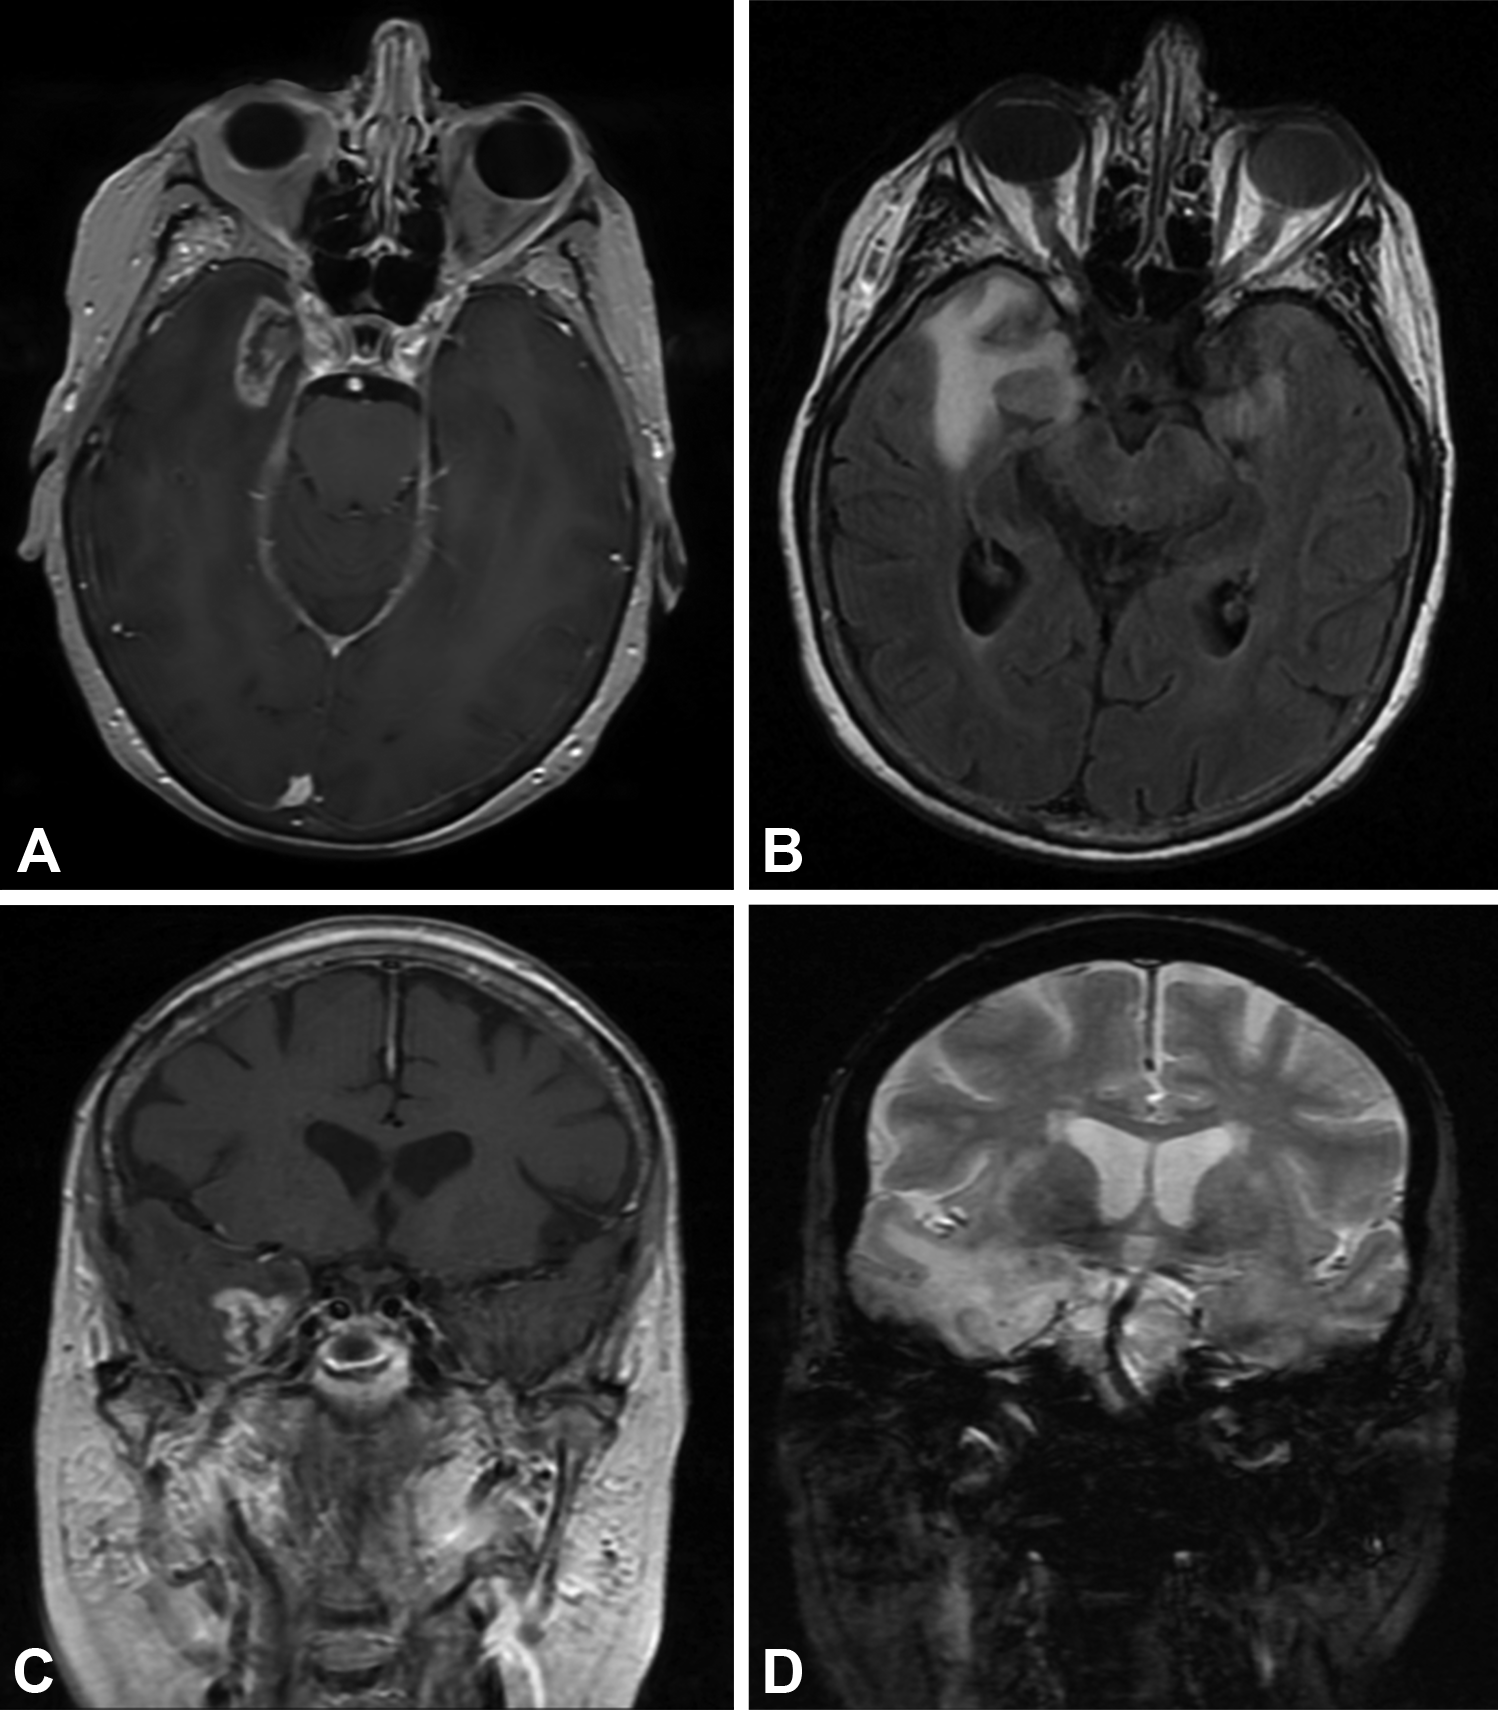

A case of postradiation necrosis in 33 years old male with resected Medical Term Radiation Necrosis new radiation modalities have made it possible to prolong the survival of. cerebral radiation necrosis or radionecrosis refers to necrotic degradation of brain tissue following intracranial or regional radiation. radiation necrosis or radionecrosis is most often encountered by pathologists on biopsy material as a late delayed manifestation,. radiation necrosis, a focal structural lesion that usually occurs. Medical Term Radiation Necrosis.

Clinical imaging for case illustration of radiation necrosis Medical Term Radiation Necrosis new radiation modalities have made it possible to prolong the survival of. radiation necrosis is a late complication of radiotherapy to the brain and generally occurs months to years after. cerebral radiation necrosis or radionecrosis refers to necrotic degradation of brain tissue following intracranial or regional radiation. radiation necrosis or radionecrosis is most often encountered by. Medical Term Radiation Necrosis.